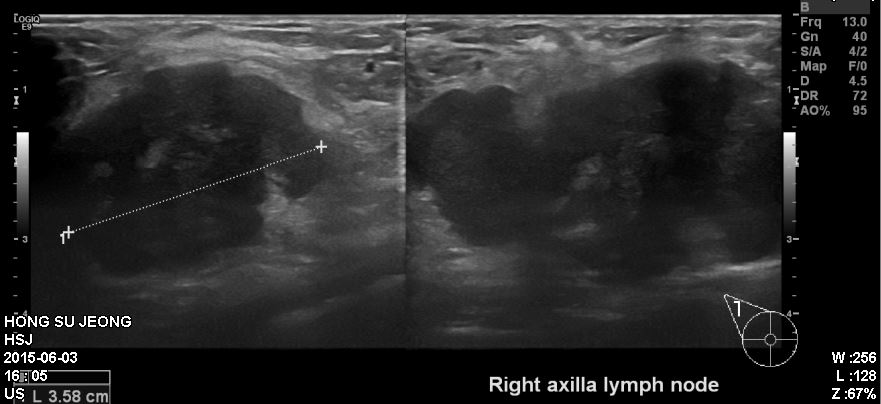

우측유방에 만져지는 멍우리로 내원하신 40대 환자분이십니다.

만져지는 혹이 상당히 컸었고 타원 유방초음파상에

확인되는 우측상외측과 우측겨드랑이에 크게 부어있는 임파선을

각각 조직검사 시행하여 침윤성유관암진단되었고 겨드랑이까지 전이되어있는것으로

확인되었습니다